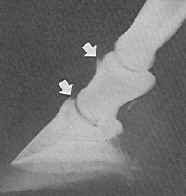

Analizuojant OCD pasireiškimą kulno sąnaryje, atvejų dažnumas kairėje ir dešinėje pusėse gana ženkliai skyrėsi. Kairės pusės pažeidimai buvo nustatyti 14 atvejų, kai tuo tarpu dešiniosios – 7, t.y., kairės pusės kulno sąnario osteochondritiniai pažeidimai nustatyti du kartus dažniau.

Tyrimui buvo surinktos rentgenogramos, kuriose atliktos kulno sąnario projekcijos 45-70o, 110-120o kryptimis. Kulno sanaryje OCD fragmentų dydis svyravo nuo pipiro iki vyšnios dydžio. Tai buvo pastebima tiek 47-70o, tiek 110-120o projekcijose. Osteochondritiniai fragmentai kulno sąnaryje buvo matomi kaip atplaišos nelygiais kontūrais, taip pat buvo rasti nelygūs sąnariniai paviršiai.

26 pav. Kulno sąnario rentgenograma

Literatūros duomenimis (Bramlage L.R., 2006), kulno sanario OCD du kartus dažniau serga patinai. Kadangi šio tyrimo metu tiriamų gyvulių lytis nebuvo žinoma, todėl ligos pasireiškimas lyties atžvilgiu nebuvo nustatytas.